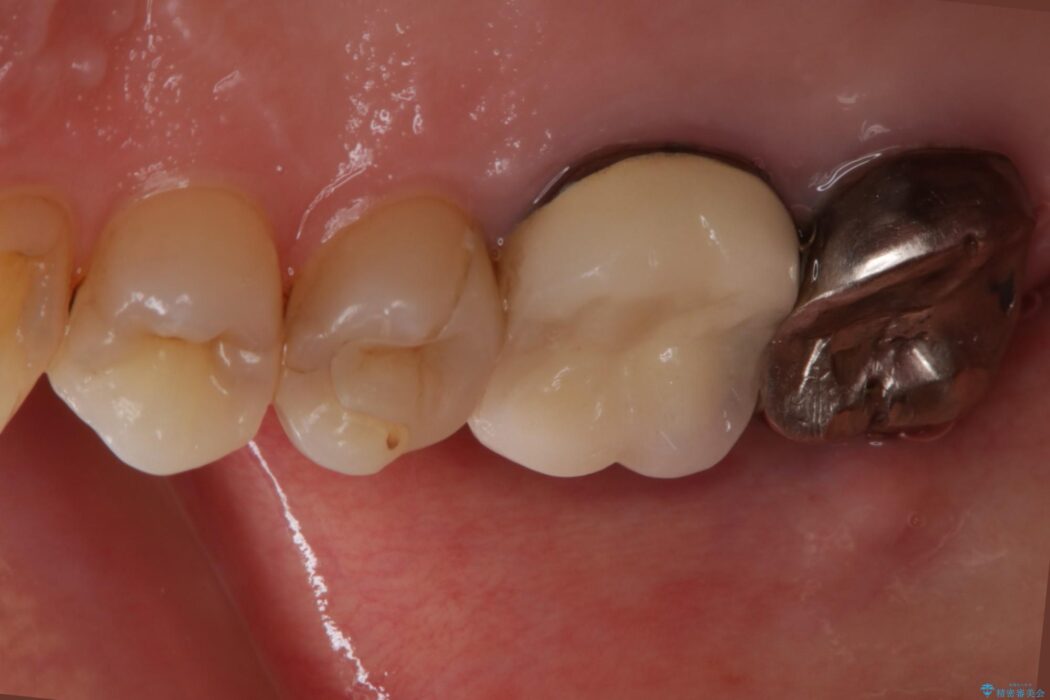

最終的にセラミッククラウンによる補綴治療を行いました。

適合の悪い補綴物は二次的な虫歯発生のリスクが高まります。

自費診療で用いられる材料は保険適応の材料に比べて、より精密で適合の良い被せ物作ることができるため、長期的な虫歯のリスクを大幅に減らすことが可能になります。